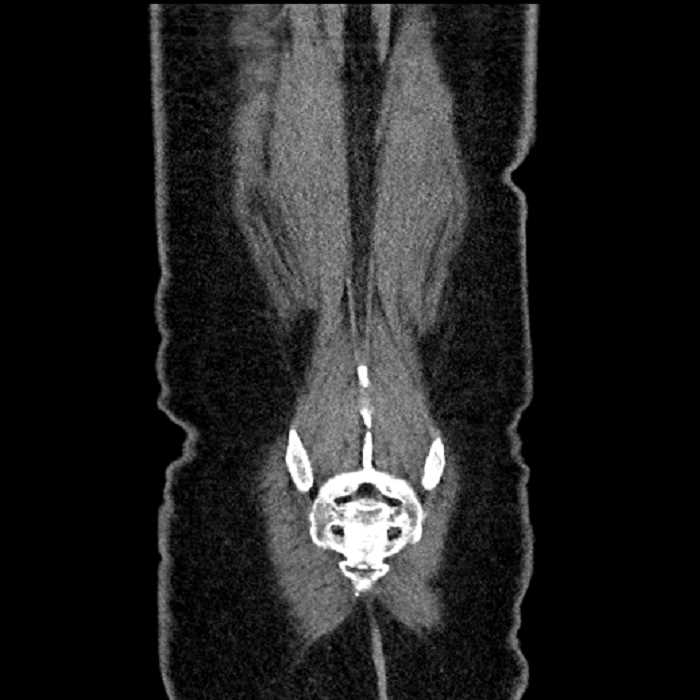

• MSK

• No acute findings

• Ankylosis of both sacroiliac joints

Hepatic abscess showing the double target sign with low density internally surrounded by a thin inner enhancing rim (red arrow) and ill-defined outer low density rim (yellow arrow). Blue arrow indicates an internal septation. Red arrows: additional smaller subcapsular abscesses. Red arrow: focal contained perforation associated with diverticulitis.